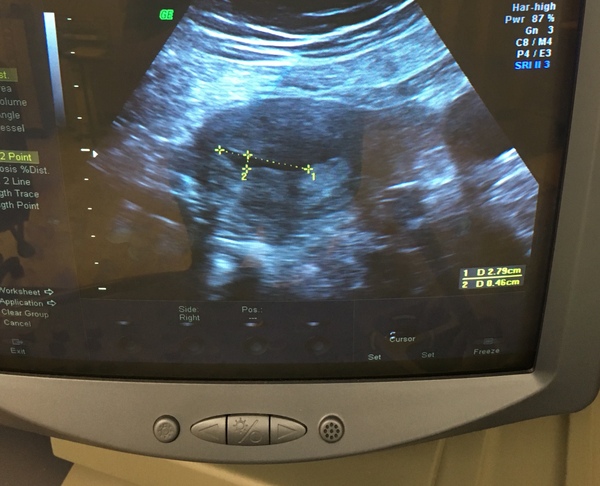

I think I’m maybe just too hopeful that it is the start of another pregnancy. After 4 weeks of the bleeding stopping I had a scan which showed a black space. They said it was probably just fluid. We had hope it could be another pregnancy. I’ve not had another scan since. We just hoped it would be over with quickly to get back to normality the body is a crazy thing.